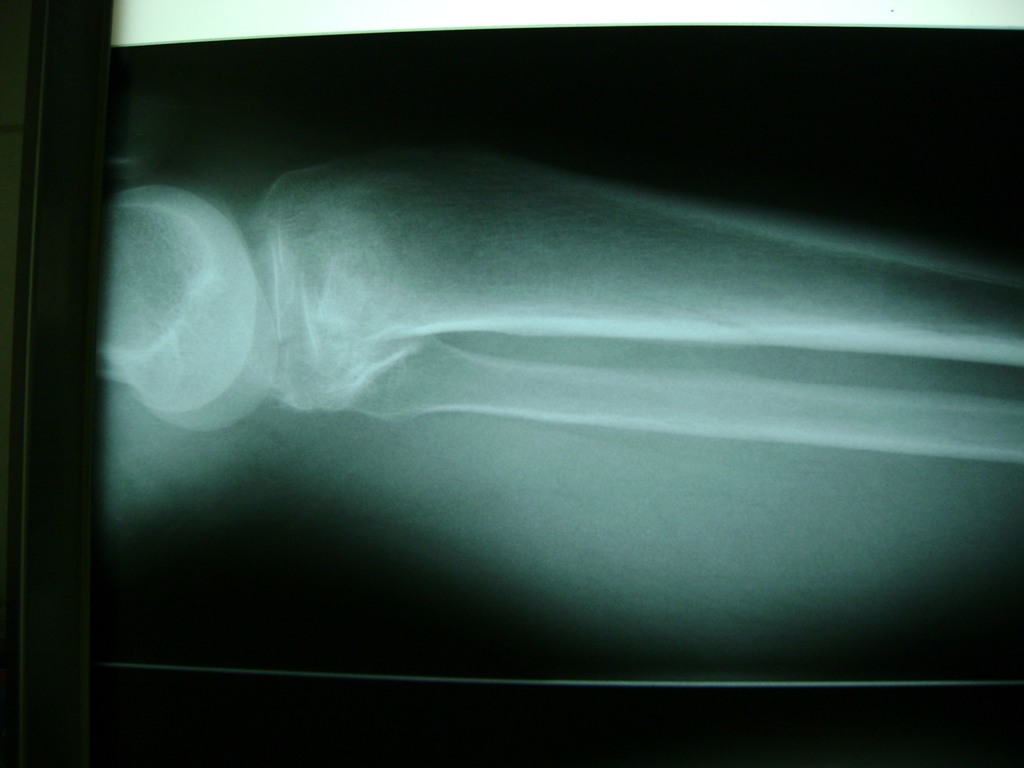

Cirugías de Calcaneo - Rodilla

La artroscopia de rodilla es un cirugía en el cual la estructura interna de la articulación es examinada ya sea para realizar un diagnostico o para realizar un tratamiento, este procedimiento se realiza utilizando un instrumento parecido a un pequeño tubo llamado artroscopio.